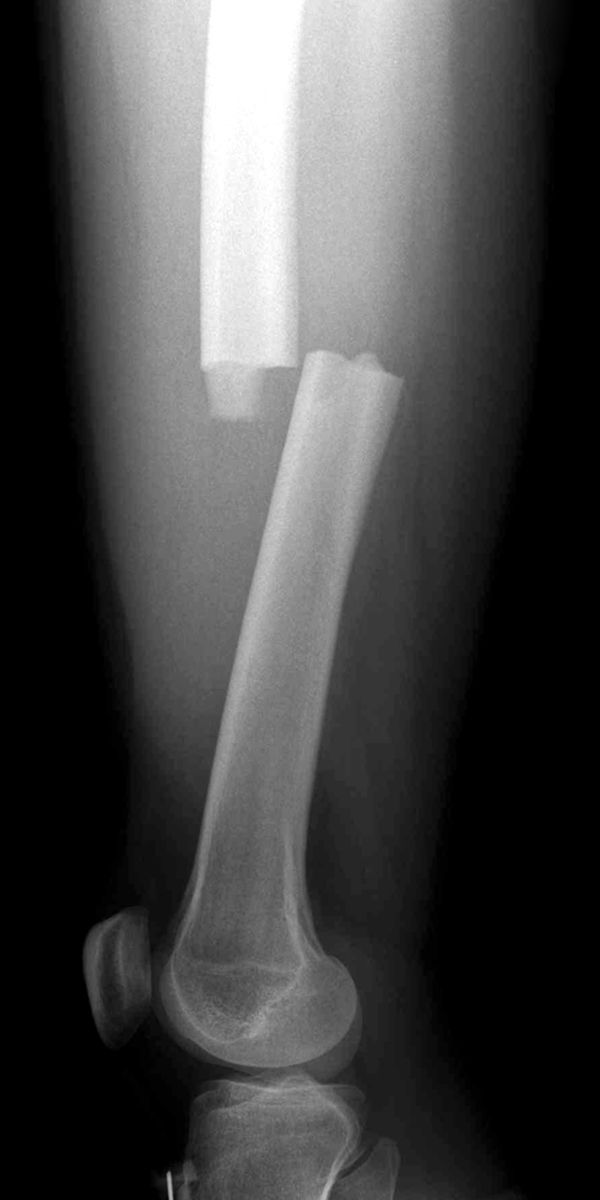

Traction splint

هو جهاز يستخدم في حاله اصابه عظمه الفخذ بكسر بشرط ان لايكون الكسر مفتوح او قريب جدا من الحوض او من الركبة.

-نلاحظ بروز العظم من تحت الجلد - وهذا في حالة الكسور الشديدة جدا.